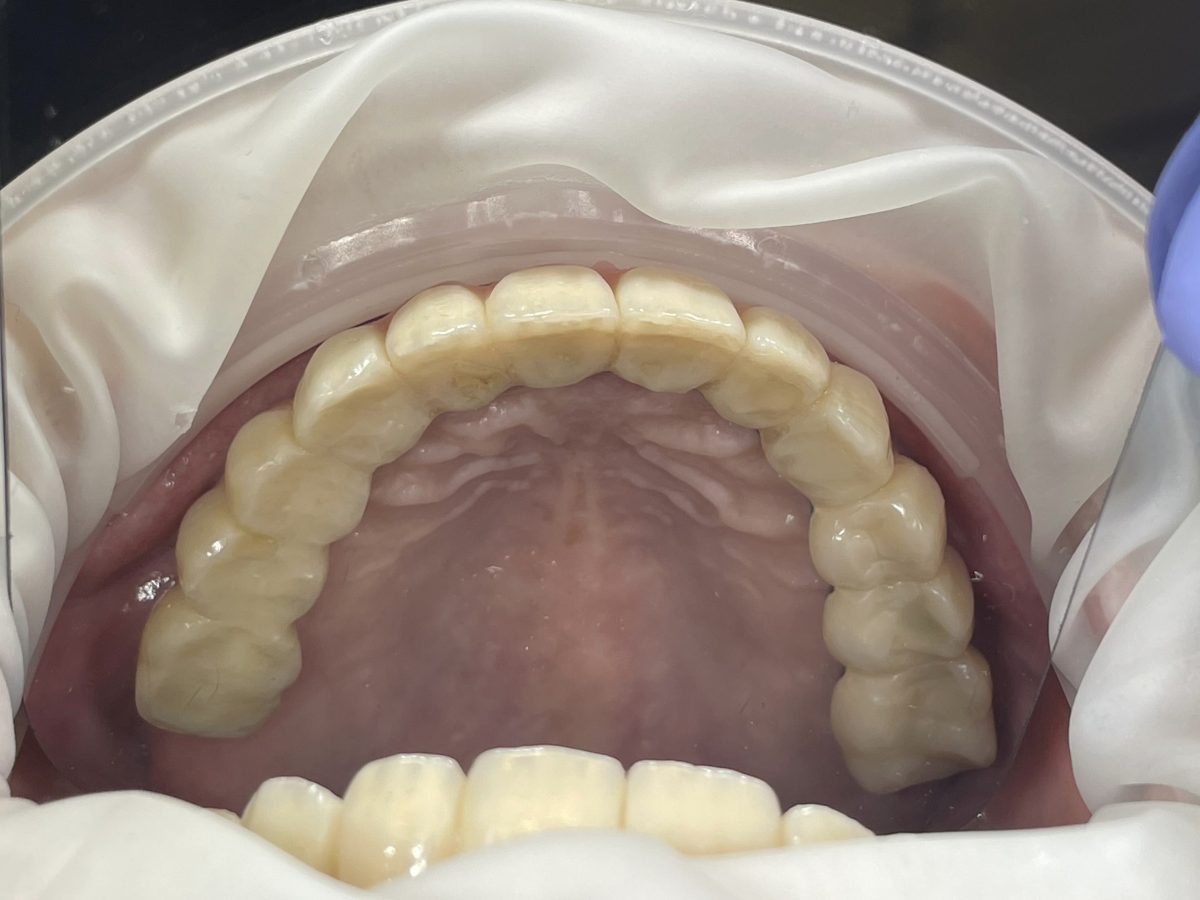

All-on-X dental implants are a full-arch restoration solution designed for patients with multiple missing, damaged, or failing teeth. The treatment uses four, five, or six dental implants to support a fixed full-arch prosthesis, restoring both function and aesthetics.

The number of implants required depends on bone condition, bite forces, and overall treatment planning.

The final full-arch prosthesis is fabricated and fitted over several appointments to optimize comfort, bite, and aesthetics.